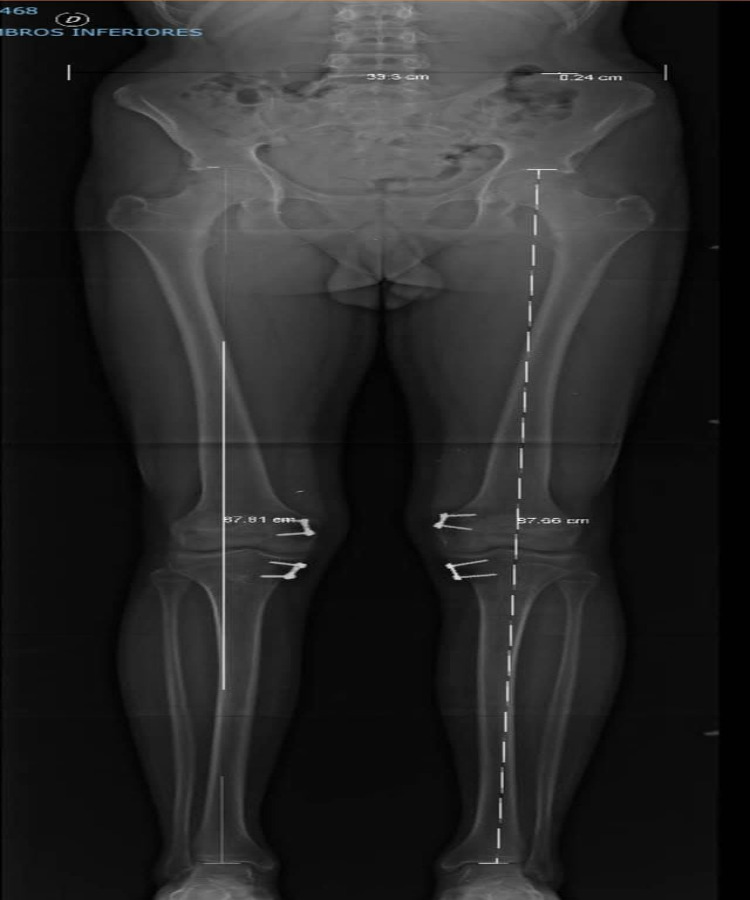

Rodillas en valgo con rótula alta

Él es mi pacientito Cristian, quien a sus 13 años me visitó para la revisión de sus rodillas porque le dolían al jugar fútbol. Le diagnosticamos rodillas en valgo con rótula alta. El tratamiento consistió en una cirugía de descenso rotuliano y crecimiento controlado de rodilla para corregir la deformidad. A los 6 meses del tratamiento, pudo correr y jugar fútbol sin problemas. Ahora tiene 15 años y ya lo di de alta.